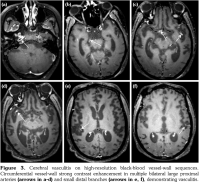

Initial brain MRI, using a standard protocol, was normal (Figures 1a and 2a). Due to rapid deterioration of the neurological status, a follow- up MRI was performed three weeks later (Figures 1b and 2b), including gadolinium administration and angiographic sequences. A mild periventricular nonspecific leukoencephalopathy and an incipient dilation of the supratentorial ventricles were observed. No abnormal contrast- enhancement was present. MRI angiography and venography showed permeability of the vessels. The patient continued to deteriorate, in a span of several weeks, despite initiating high-dose intravenous methylprednisolone. The clinical suspicion of vasculitis was raised and a third MRI was performed, at 3.5 months from the onset, with a specific protocol including vessel-wall three-dimensional (3D)-high-resolution pre- and post-contrast black-blood sequences. This MRI showed severe progression of the leukoencephalopathy, and associated atrophy with marked dilation of the ventricles and the subarachnoid spaces (Figures 1c and 2c). High-resolution vessel-wall sequences showed multiple arterial segments with concentric contrast enhancement of the wall, of proximal and distal distribution (Figure 3), compatible with vasculitis. A treatment with high-dose intravenous cyclophosphamide was started. Clinical follow- up revealed a progressive improvement of the drowsiness with eventually stabilized neurological status, but the cognitive deficit was already extremely impaired. The fourth MRI exam, at seven months from the clinical onset, showed even more severe atrophy (Figures 1d and 2d). A comparative of the hippocampal formation, crucial for the memory circuit, showed normal features on the first MRI (Figure 2e) and marked “knife blade” atrophy on the last study (Figure 2f). Concomitant diseases, including cerebrovascular and cardiovascular events, were ruled out.